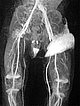

Nachdem am Ende des 3. Lebensjahres immer noch keine Rückbildungstendenz des Tumors sichtbar war, wurde nach einer Biopsie eine Embolisation zur Induktion einer Involution durchgeführt. Die Digitale Subtraktionsangiographie (DSA) zeigt einen Mikrokatheter superselektiv in einem Tumorgefäß. Der Tumor ist stark perfundiert und lobuliert, sehr früher venöser Abstrom, typisch für ein NICH.

Partikelembolisation mit sphärischen Partikeln der Größe 250 Mikrometer über den superselektiv in den Tumor eingeführten Mikrokatheter.

Weitere Tumorgefäße mit blush-artigem, diffusem Enhancement, typisch für Gefäßtumor/NICH. All diese Gefäße müssen selektiv embolisiert werden um eine Involution zu induzieren.

Weitere selektive Partikelembolisation. Die mit Kontrastmittel gemischten Embolisationspartikel verbleiben in den Tumorgefäßen.

Auch in der Übersichtsangiographie über die linke Arteria iliaca externa zeigt sich keinerlei Perfusion des Tumors mehr, die Tumorvaskularisation ist somit erfolgreich superselektiv vollständig verschlossen. Alle nicht pathologischen Arterien sind erhalten.